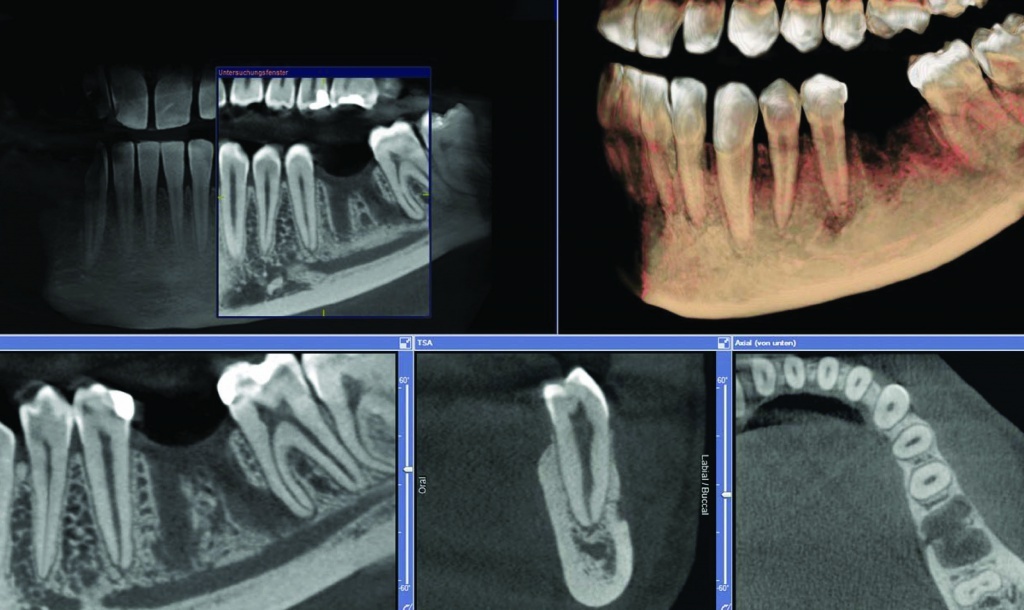

3D-снимок зубов. Трехмерный снимок зубов создается с помощью обновленного ортопантомографа, оснащенного современнейшим программным обеспечением, которое используется для обработки получаемых данных. Этот вариант компьютерной томографии оказывает намного меньшую лучевую нагрузку на организм пациента и может использоваться как на раннем этапе диагностики, так и во время лечения зубов.

Компьютерная томография. Дентальная КТ используется для получения снимка зубов в нескольких плоскостях и с разной глубиной сканирования. Преимуществом компьютерной томографии является отсутствие искажений на полученном снимке. В отличие от пленочного рентген-аппарата томограф не оказывает сильной лучевой нагрузки на ткани, поэтому разрешен даже для исследования зубов беременных женщин и детей.